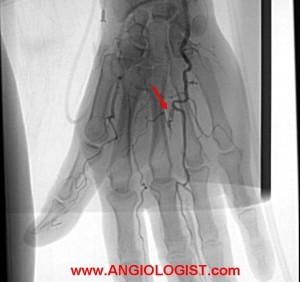

Imaging studies are often needed to make the diagnosis of Buerger’s disease. Once angiography was mandatory. Today MRA and CTA can be utilized. However, these tests are often not accurate for the tips. Therefore angiography is still often used. Typical angiography shows affected segments and normal segments in between. This is called “skipped lesions”. There is tapering and cutoff of the vessels. Magnification may show a corkscrew appearance of collaterals. A third characteristic of thromboangiitis obliterans on angiography is Martorell’s sign which are direct collaterals. Angiographic images have to be taken twice, with and without vasodilators. The purpose is to make sure abnormal segments are not due to vasoconstriction.